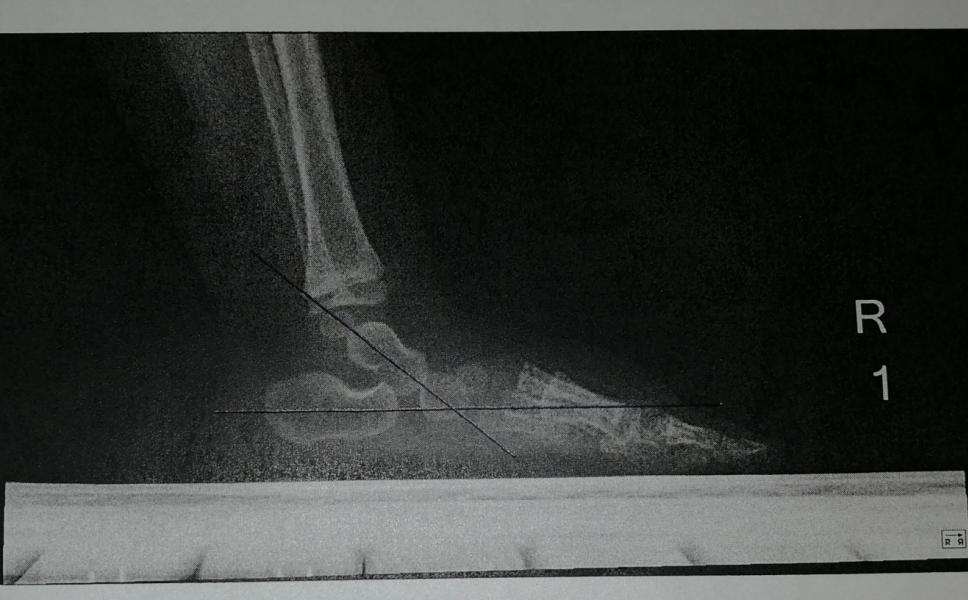

Ахеренная мать. У ребёнка сломаны обе ноги. Подумаете вы, увидев нас на улице или просто эти фотографии. Но это не так.

Кто-нибудь слышал про Косой таран? Вот и я нет. Это врождённая патология стоп.

Я расскажу здесь нашу историю, так как я искала и ничего не нашла и может кому-то она поможет.

Мамы которые столкнутся с такой-же проблемой вы можете написать мне, для моральной поддержки и подробной информации, моя страница в инстаграм daria_kova174

ЧАСТЬ 1.

Нам потребовалось 3 ортопеда, чтобы ...